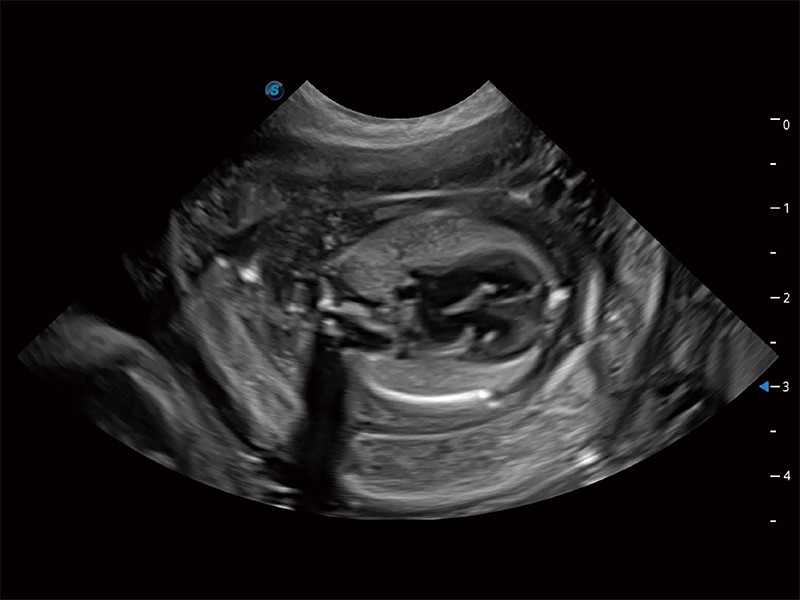

动物是人类最亲密的朋友和最值得信赖的伙伴。哈哈体育官网也一直致力于探索动物专用的超声影像解决方案。全新推出的ProPet系列,是哈哈体育官网在动物超声影像智能化、专业化、精准化的一次跨越式革新。动物不能用言语来表述自己的不适,通过超声影像,ProPet系列搭建了动物医生与不同物种沟通的“桥梁”,为动物医生注入了“治愈之力”。 ProPet 80 是哈哈体育官网匠心打造的一款高端动物专用彩超,采用性能卓越的全新硬件架构,极大提升超声系统的运行效率和数据处理能力,帮助动物医生从容应对日益增多的挑战性病例和日益多样化的临床需求。

高性能和先进的临床应用工具可以为动物医生提供临床信心。ProPet 80 搭载了先进的腹部和浅表应用工具,帮助医生在日常临床实践中发挥前所未有的作用。

ProPet 80 全新的动物超声智能软件和丰富的探头群,为动物医生提供了高清晰度和精细分辨率的图像,无论在宠物、马科、畜牧还是实验室动物等应用中都可以轻松应对,为您的日常工作带来满意的体验。